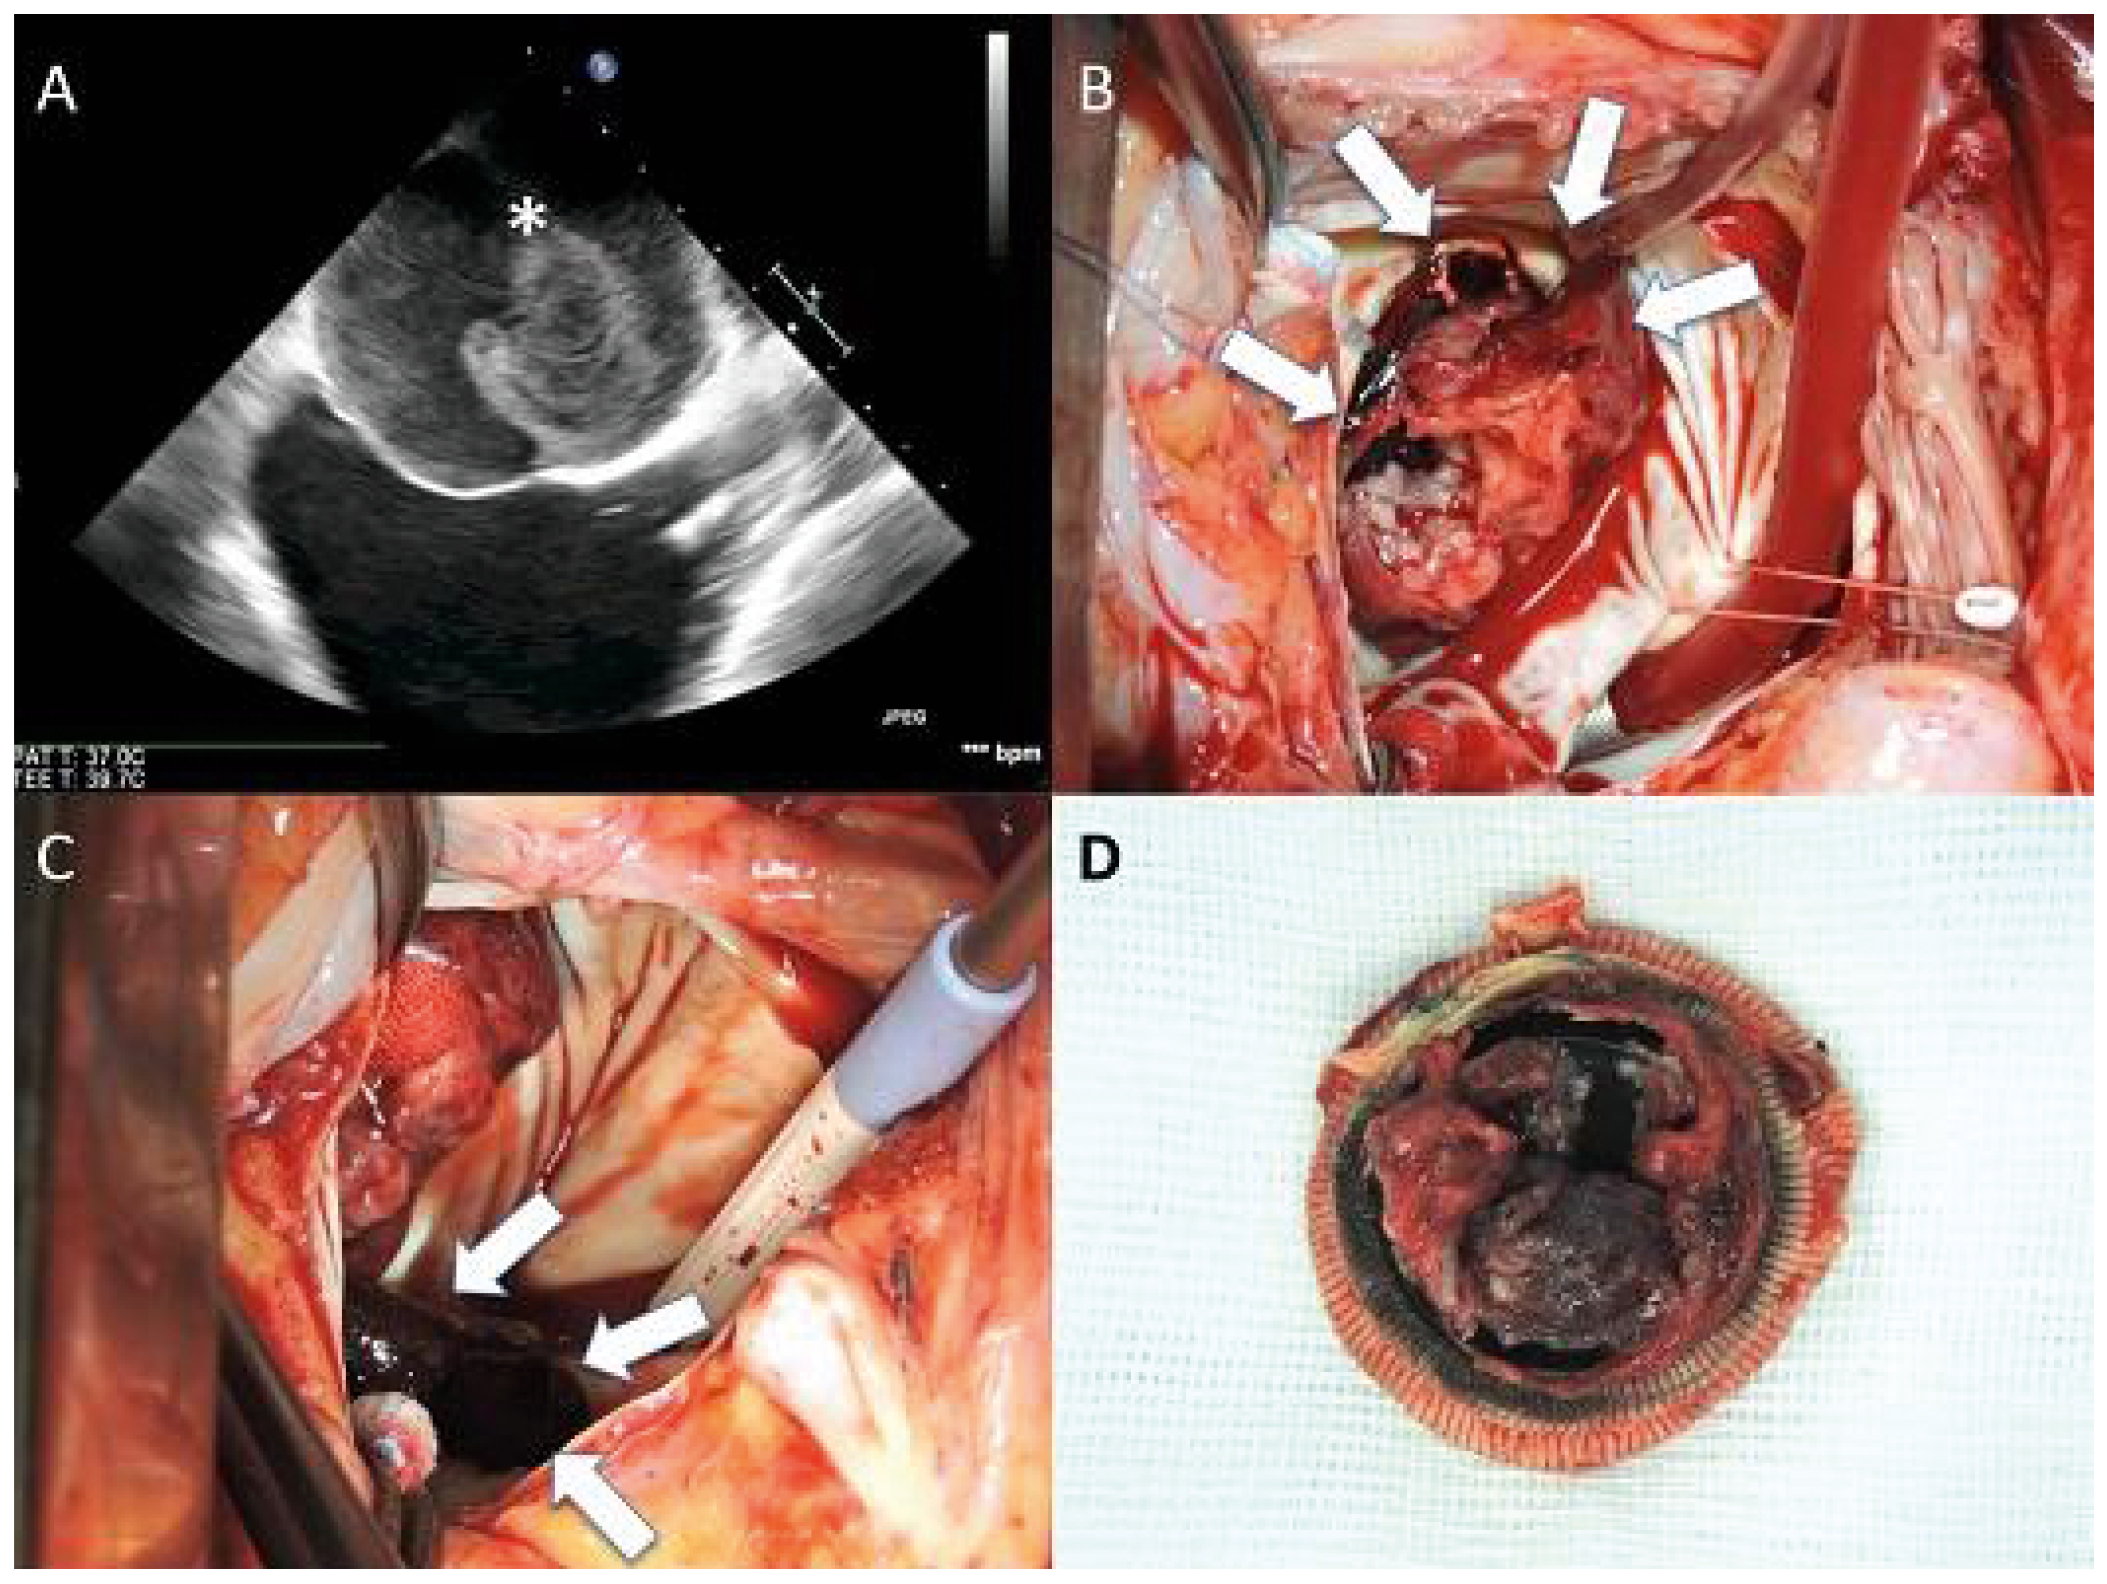

Methods: A boy at the age of two years and 5 months was referred to our hospital because of the presence of a severe aortic regurgitation (AR) associated with sub-aortic membrane. Two years ago, at the age of 5 months, he was operated in another centre for ASO and VSD closure for d- transposition of great arteries (D-TGA) with ventricular septal defect (VSD). Echocardiography (Figure 1) showed a thickened aortic neo-valve with severe eccentric regurgitation with diastolic reflux of the descending aorta. A cardiac CT was performed and showed very tortuous thoracic aorta and discreet stretching of the pulmonary arteries with a mass aspect due to the LeCompte maneuver. The thoracic aorta appearing “crushed” by the LeCompte maneuver.

Results: Redo sternotomy was performed, the heart and great vessels were dissected and exposed. Under the CPB, neo-pulmonary root was transected (pulmonary root was on anterior after the LeCompte maneuver), aorta was clamped and selective cardioplegia was administrated. We note a retracted and shortened anterior leaflet caused by VSD patch. Other two leaflets were normal. After the resection of the anterior leaflet and sub-aortic membrane, we started the aortic valve reconstruction. The distance between commissures was measured with special Ozaki sizing device. Because of the missing of the autologous pericardium, we used a CardioCel® patch (bovine pericardium). The size corresponding to the measured value was cut. The annular margin of the patch leaflet was sutured with 5-0 Prolen running sutures to the annulus. Commissural coaptation was secured with additional 5-0 Prolen sutures. The aortotomy was closed. Intraoperative echocardiography showed an excellent result.